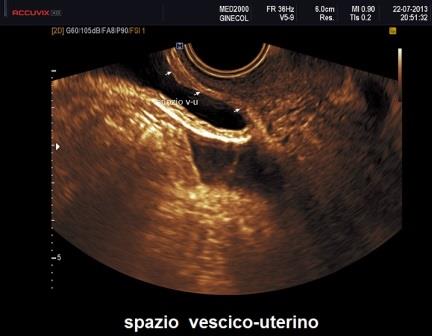

I noduli endometriosici della vescica si presentano come formazioni ipo o isoecogene localizzate più frequentemente nello spazio vescico-uterino a livello della base vescicale e meno frequentemente interessano la cupola; a volte si manifestano come noduli ad ecostruttura disomogenea con piccole aree anecogene ("bubble-like") di forma sferica o a virgola che improntano il profilo della plica vescico-uterina. E' importante valutare la presenza di impianti a livello del trigono vescicale e l'eventuale interessamento dei meati ureterali che può essere studiato osservando con il color Doppler il getto di urina in vescica. Spesso i noduli vescicali obliterano lo spazio vescico-uterino per cui è utile ricercare lo scorrimento tra parete uterina anteriore e superficie vescicale.